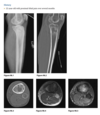

Adolescent child with pain in the leg, another radiograph in the humerus

A

well-defined, eccentric, radio-

lucent lesion with a thin, sclerotic border adjacent

to the cortex of the distal tibia.

Repeat 7 yrs later shows well defined sclerotic lesion in same location.

Humerus radiograph shows identical lesion with pathological fracture

Diagnosis: Fibrous cortical defect or NOF

> 2cm = NOF and <2cm = FCD.

Can be polyostotic - associated with NF, FD, Jaffe-Campanacci syndrome.

Lesions originally

arise adjacent to the physis, and as limb lengthen-

ing occurs, they migrate away from the joint.

typical FCD or NOF is radiolucent; has a thin, scle-

rotic margin; and shows no periosteal reaction.

Rarely, it may be expansile or undergo pathologic

fracture.

Involutes during adolescence and becomes sclerotic.